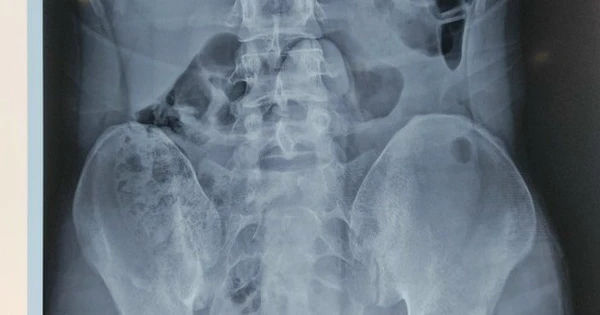

Chuyện bất ngờ: Trực tràng nam thanh niên chứa kỳ đồ chơi tình dục

Nam thanh niên gặp sự cố khó đỡ khi một dụng cụ tình dục dài 25cm bị mắc kẹt trong trực tràng, gây đau đớn kinh khủng tại vùng bụng và hậu môn